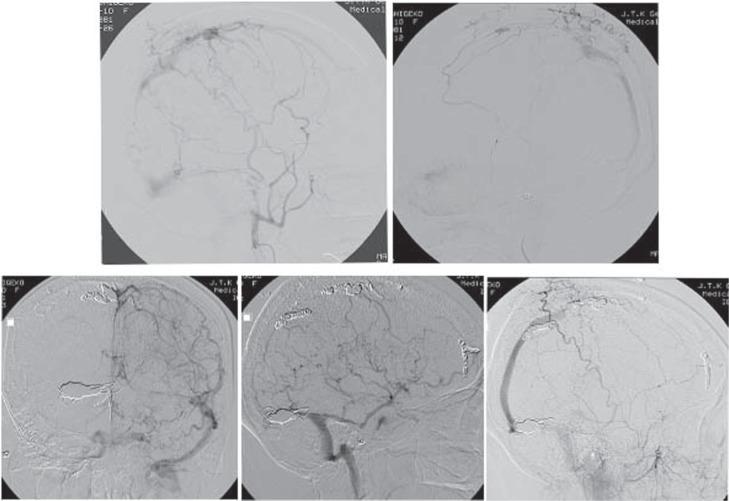

A 67-year-old female presented with multiple dural arteriovenous fistulas (AVFs) manifesting as dementia rapidly progressing over 2 months. The initial diagnosis was Creutzfeldt-Jakob disease based on the acute clinical course. However, angiography eventually revealed multiple dural AVFs involving the bilateral convexities to the superior sagittal sinus and the right transverse-sigmoid sinus. Endovascular treatment combining arterial and venous embolization in multiple stages proved to be effective, as the hemodynamic pathology improved, and the patient recovered from dementia. The cause of the dementia was thought to be venous hypertension in the deep white matter induced by the dural AVFs. Dural AVFs should be included in the differential diagnosis of rapidly progressive dementia.

一名67岁女性因多发硬脑膜动静脉瘘(AVF)就诊,表现为在2个月内迅速进展的痴呆。基于急性临床病程,初步诊断为克雅氏病。然而,血管造影最终显示多发硬脑膜AVF累及双侧凸面至上矢状窦以及右侧横窦-乙状窦。多阶段联合动脉和静脉栓塞的血管内治疗被证明是有效的,随着血流动力学病变改善,患者从痴呆中康复。痴呆的原因被认为是硬脑膜AVF引起的深部白质静脉高压。硬脑膜AVF应纳入快速进展性痴呆的鉴别诊断。